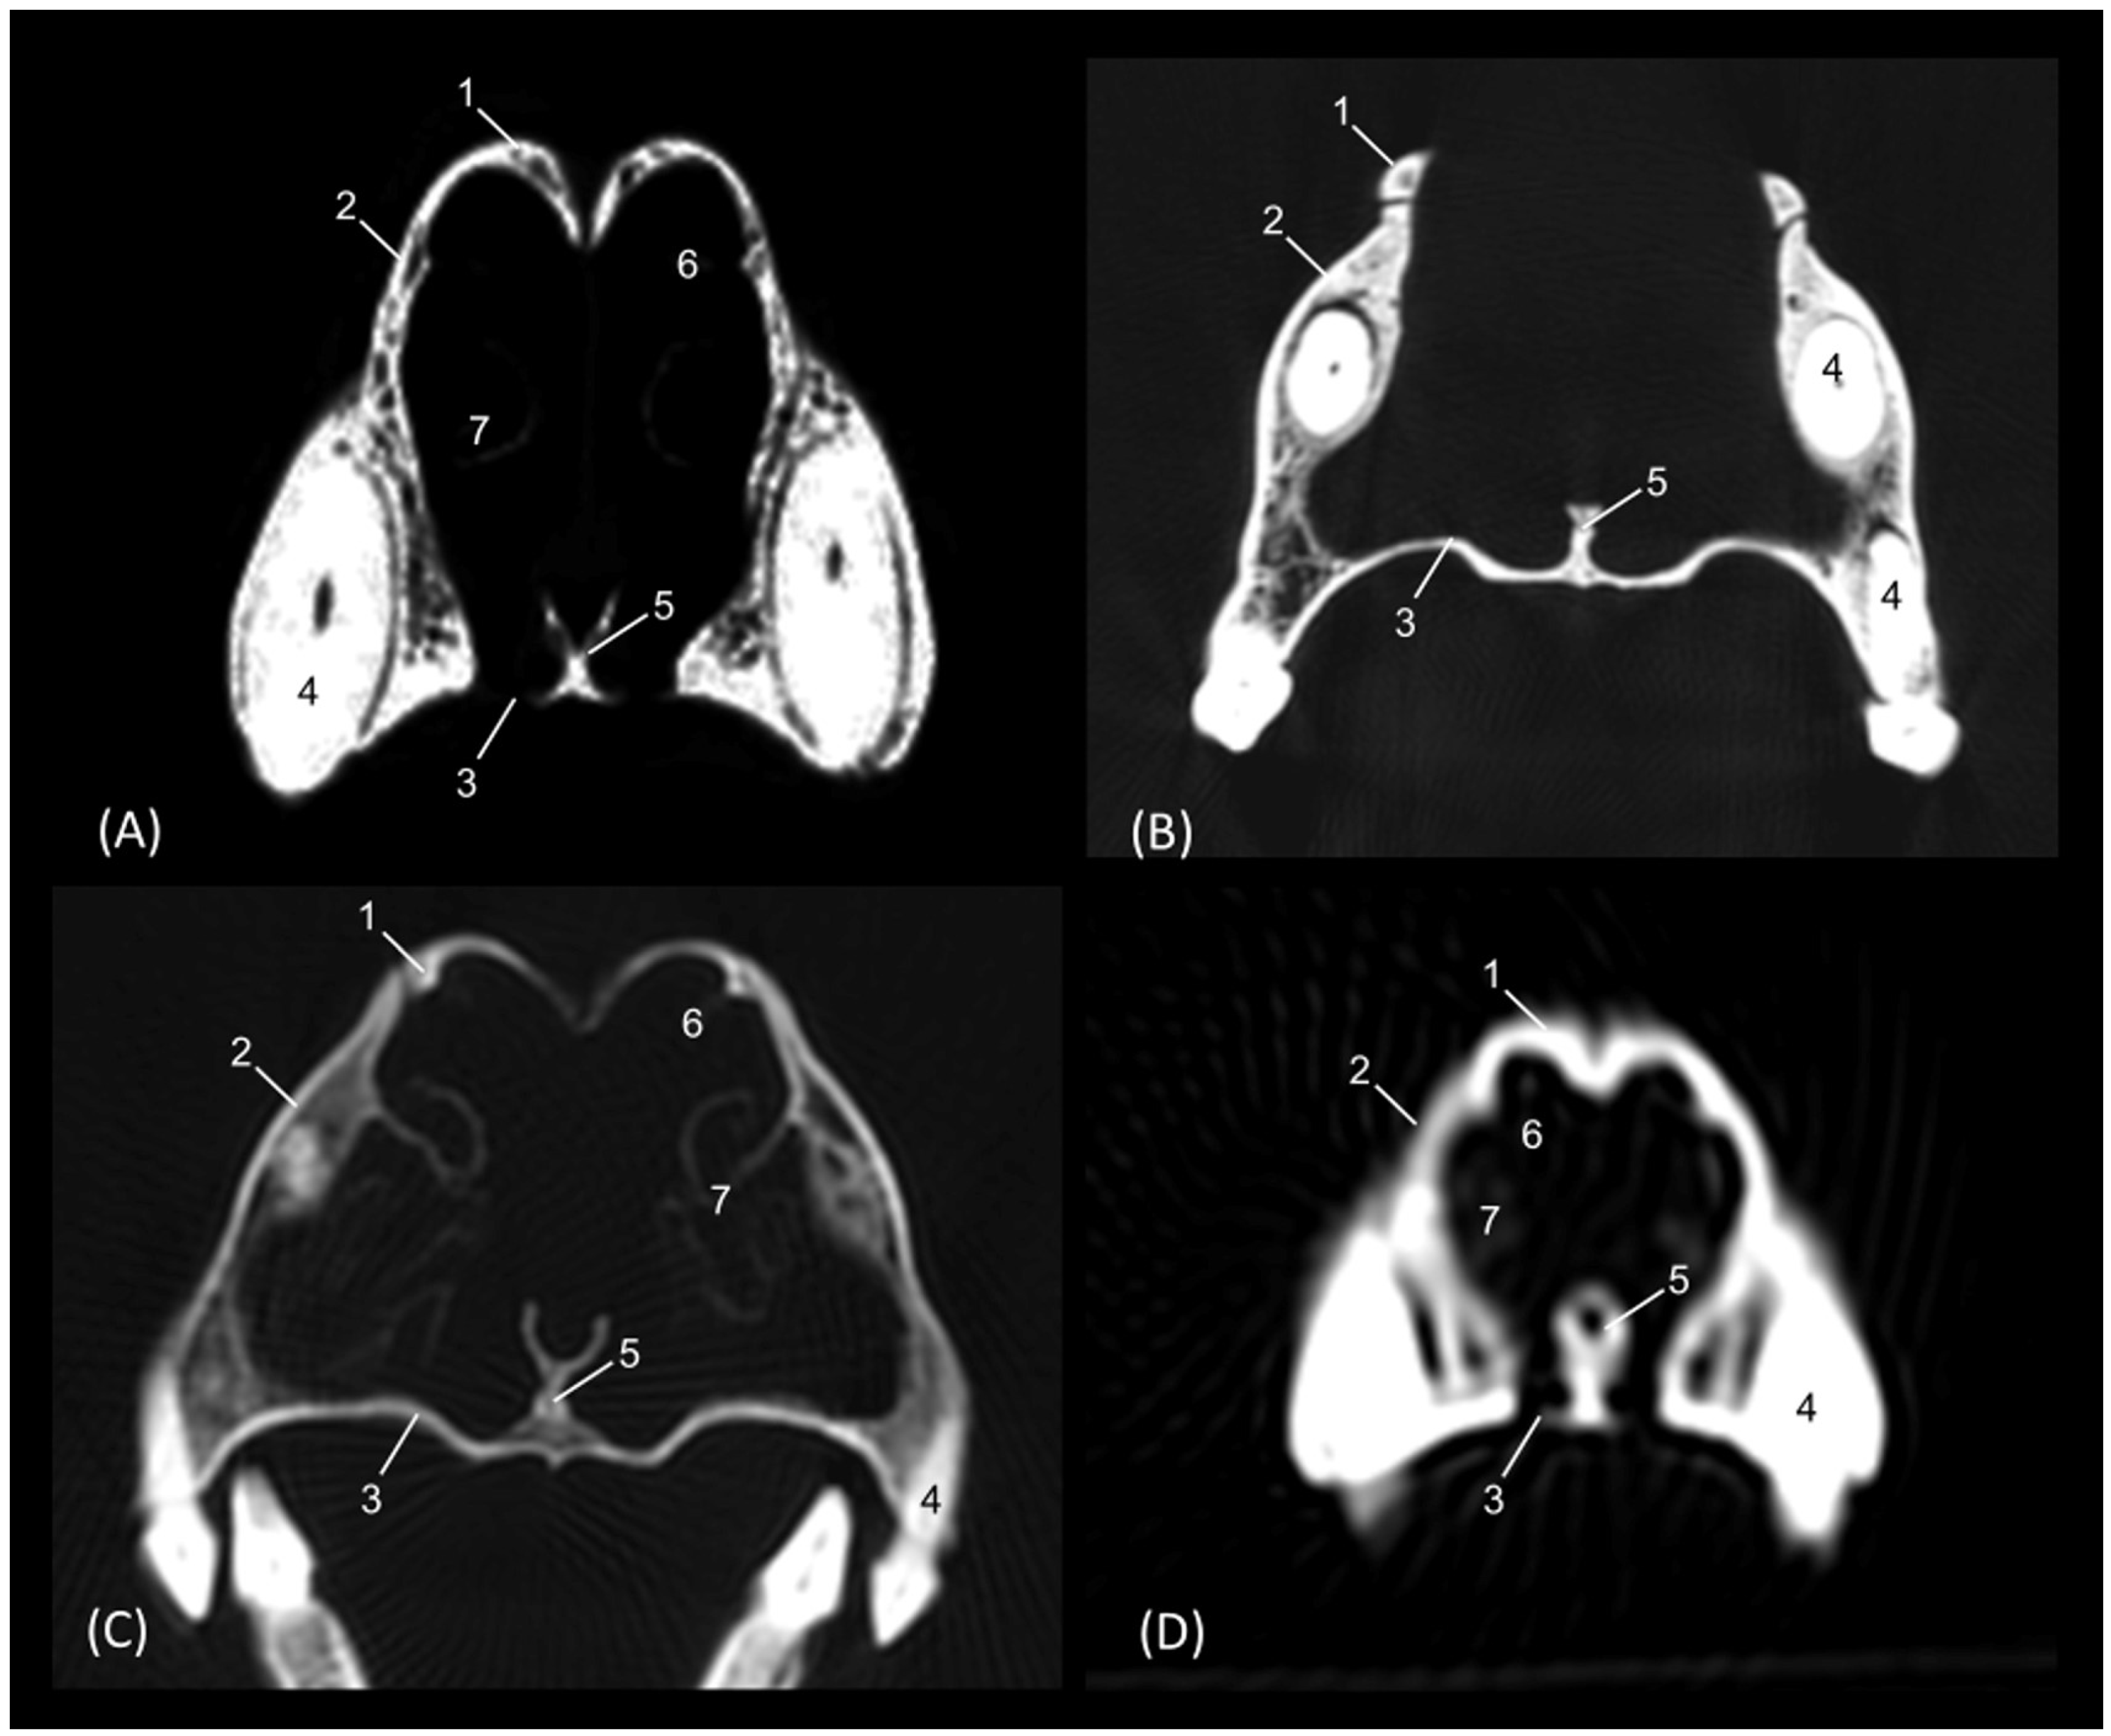

Through tomographic studies carried out on the heads of felids, 3D reconstruction models were developed using 3D MIP (Figure 27, Figure 28, Figure 29 and Figure 30) and VR (Figure 31, Figure 32, Figure 33 and Figure 34) applications. MIP reconstruction techniques allowed us to clearly visualize the internal dimension of each structure of the nasal cavity and paranasal sinuses. Sagittal, transverse, and dorsal views of the four felids were selected.

Starting with the leopard (Figure 27), the extension of the frontal sinus was observed in the sagittal and transverse planes. In this sinus, the very limited ectoturbinates could be visualized, especially in the transverse image. The dorsal nasal concha was observed throughout its entire length, reaching its maximum dimension in the middle area of the nasal cavity and becoming thinner as it approached its rostral end. The ventral nasal concha was limited to the rostral half of the nasal cavity. With this technique, the extension of the choana could also be clearly seen.

Figure 27. OsiriX MIP reconstructed CT images of the leopard’s head. (A) Sagittal image. Left lateral view. (B) Transverse image. Caudal view. (C) Dorsal image. Dorsal view. 1. Incisive bone; 2. Nasal bone; 3. Maxilla; 4. Frontal bone: external plate; 5. Frontal bone: internal plate; 6. Frontal bone: orbital surface; 7. Ethmoid bone: tectorial plate; 8. Ethmoid bone: cribriform plate; 9. Frontal sinus; 10. Frontal sinus: septum; 11. 1st ectoturbinate; 12. 2nd ectoturbinate; 13. 3rd ectoturbinate; 14. Dorsal nasal concha; 15. Middle nasal concha; 16. 3rd endoturbinate; 17. 4th endoturbinate; 18. Ventral nasal concha; 19. Ethmoid bone: perpendicular plate; 20. Nasal septum; cartilage; 21. Vomer; 22. Zygomatic bone: body; 23. Sphenoidal sinus; 24. Choana; 25. Palatine bone: horizontal and perpendicular plate; 26. Presphenoid bone.

Figure 28 represents the MIP reconstruction of the lion’s head. In the sagittal and dorsal planes, the route and dimensions of the ethmoturbinates were observed. The sphenoidal sinus was perfectly located and limited in the sagittal plane, just as the limits of the frontal sinus could be clearly outlined.

Figure 28. OsiriX MIP reconstructed CT images of the lion’s head. (A) Sagittal image. Left lateral view. (B) Transverse image. Caudal view. (C). Dorsal image. Dorsal view. 1. Incisive bone; 2. Nasal bone; 3. Maxilla; 4. Frontal bone: external plate; 5. Frontal bone: internal plate; 6. Frontal bone: orbital surface; 7. Ethmoid bone: tectorial plate; 8. Ethmoid bone: cribriform plate; 9. Frontal sinus; 10. Frontal sinus: septum; 11. 1st ectoturbinate; 12. 2nd ectoturbinate; 13. 3rd ectoturbinate; 14. Dorsal nasal concha; 15. Middle nasal concha; 16. 3rd endoturbinate; 17. 4th endoturbinate; 18. Ventral nasal concha; 19. Nasal septum: ethmoid bone (perpendicular plate); 20. Nasal septum; cartilage; 21. Vomer; 22. Zygomatic bone: frontal process; 23. Sphenoidal sinus; 24. Choana; 25. Palatine bone: horizontal and perpendicular plate; 26. Presphenoid bone.

The MIP of the cheetah head is represented in Figure 29. The frontal sinus is considerably larger in this species, as is the sphenoidal sinus, which is proportionally much larger than in the other species examined.

Figure 29. OsiriX MIP CT reconstruction images of the cheetah’s head. (A) Sagittal image. Left lateral view. (B) Transverse image. Caudal view. (C) Dorsal image. Dorsal view. 1. Incisive bone; 2. Nasal bone; 3. Maxilla; 4. Frontal bone: external plate; 5. Frontal bone: internal plate; 6. Frontal bone: orbital surface; 7. Ethmoid bone: tectorial plate; 8. Ethmoid bone: cribriform plate; 9. Frontal sinus; 10. Frontal sinus: septum; 11. 1st ectoturbinate. 12. 2nd ectoturbinate; 13. 3rd ectoturbinate; 14. Dorsal nasal concha; 15. Middle nasal concha; 16. 3rd endoturbinate; 17. 4th endoturbinate; 18. Ventral nasal concha; 19. Nasal septum: ethmoid bone (perpendicular plate); 20. Nasal septum; cartilage; 21. Vomer; 22. Zygomatic bone: frontal process; 23. Sphenoidal sinus; 24. Choana; 25. Palatine bone: horizontal and perpendicular plates; 26. Presphenoid bone.

Finally, the MIP reconstruction of the domestic cat’s head is shown in Figure 30. The frontal sinus in this species, also proportionally large, deepens to more ventral levels than in the other felids. The ectoturbinates could also be clearly seen in the sagittal and transverse images. Both the path and the width of the nasopharynx (pars nasalis pharyngis) could also be observed extending caudal from the choana.

Figure 30. OsiriX MIP reconstruction images of the cat’s head. (A) Sagittal image. Left lateral view. (B) Transverse image. Caudal view. (C) Dorsal image. Dorsal view. 1. Incisive bone; 2. Nasal bone; 3. Maxilla; 4. Frontal bone: external plate; 5. Frontal bone: internal plate; 6. Frontal bone: orbital surface; 7. Ethmoid bone: tectorial plate; 8. Ethmoid bone: cribriform plate; 9. Frontal sinus; 10. Frontal sinus: septum; 11. 1st ectoturbinate. 12. 2nd ectoturbinate; 13. 3rd ectoturbinate; 14. Dorsal nasal concha; 15. Middle nasal concha; 16. 3rd endoturbinate; 17. 4th endoturbinate; 18. Ventral nasal concha; 19. Nasal septum: ethmoid bone (perpendicular plate); 20. Nasal septum: cartilage; 21. Vomer; 22. Zygomatic bone: body; 23. Sphenoidal sinus; 24. Choana; 25. Palatine bone: horizontal and perpendicular plate; 26. Presphenoid bone.